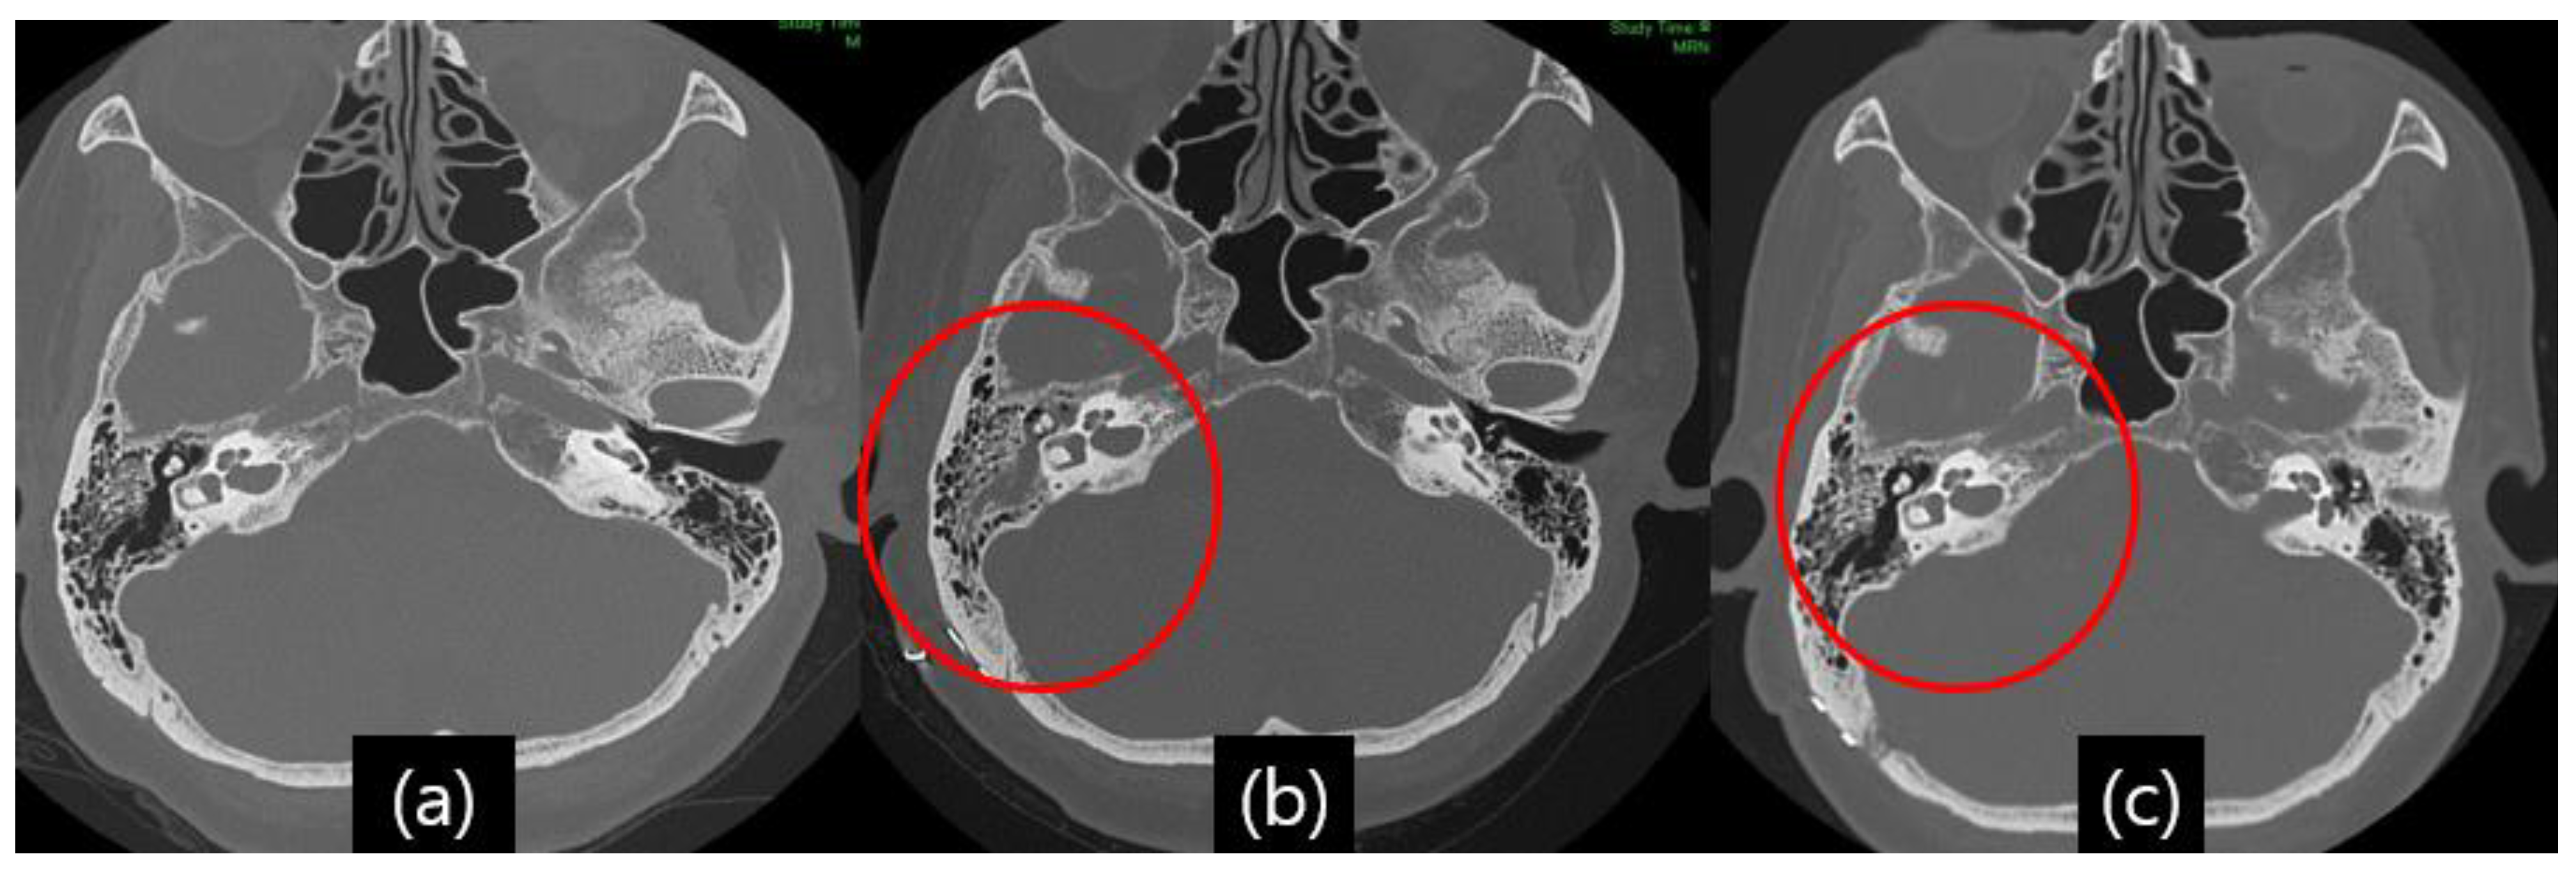

Illustrative Case